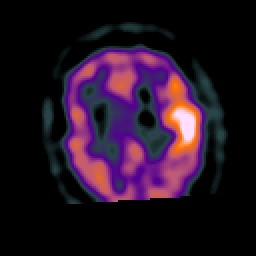

Subacute Stroke, overlay -- Slice #18

[Home][Help][Clinical] Slice 18